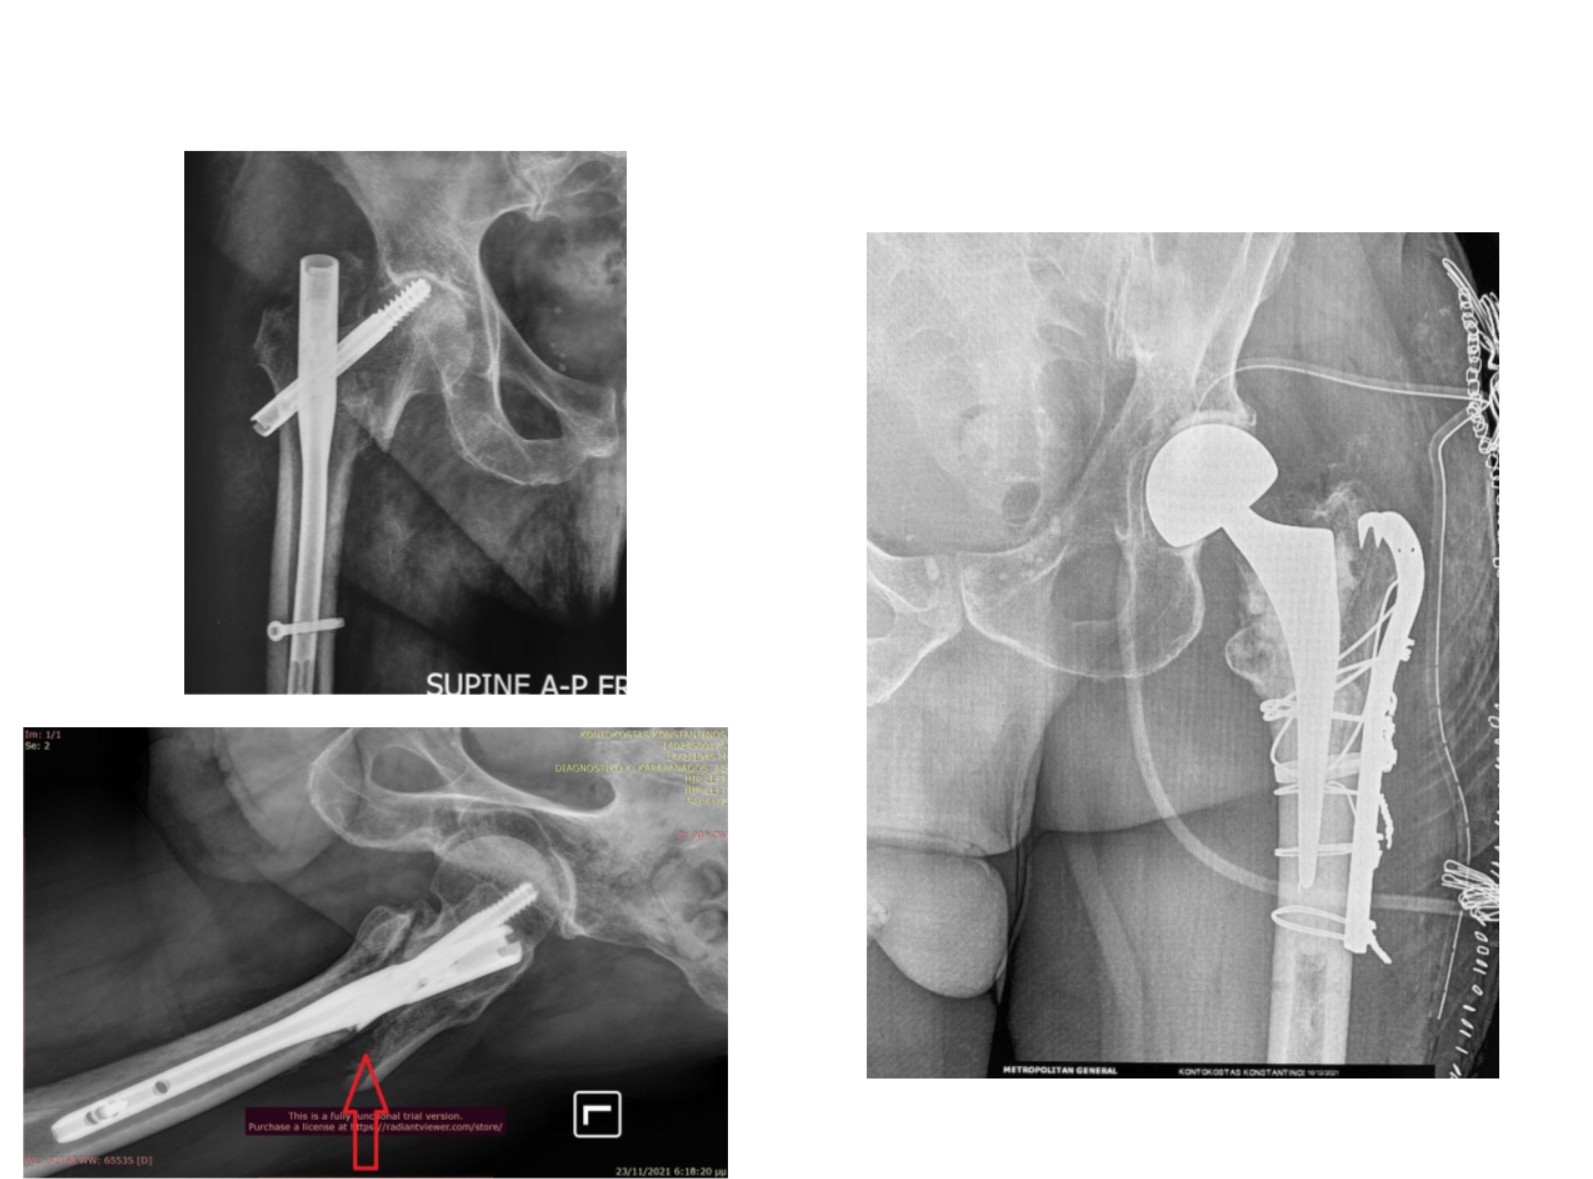

Χωρίς ικανή εμπειρία, επιπλοκές μπορεί να συμβούν: στην εικόνα 13, στην αριστερή πλευρά ημιαρθροπλαστική AMIS στην οποία τοποθετήθηκε ολόκληρος ο στυλεός του μηριαίου εκτός του αυλού. Ο ασθενής κινητοποιήθηκε την επομένη με αφόρητο πόνο σε εξάρθρημα. Όσο κι αν φαίνεται απίθανο, είναι μια επιπλοκή που μπορεί να συμβεί σε μη έμπειρα χέρια. Δεξιά στην εικόνα φαίνεται ο ορθός τρόπος τοποθέτησης του στυλεού.

Στην εικόνα 14, κατά τη διάρκεια ημιαρθροπλαστικής AMIS, η απειρία οδήγησε σε εργώδεις προσπάθειες ανάταξης και κάταγμα κοτύλης. Αντιμετωπίστηκε στην κλινική μας με ειδικού τύπου πρόθεση κοτύλης του τύπου της αναθεώρησης αρθροπλαστικής (revision hip arthroplasty)